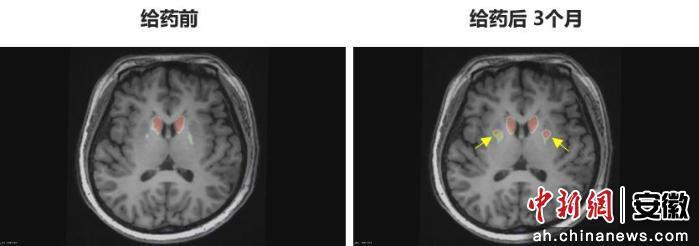

今年6月,李女士在中國科學技術大學附屬第一醫院接受了NCR201干細胞移植治療,該療法利用誘導多能干細胞(iPSC)衍生的多巴胺能神經前體細胞。三個月后,她成為全球首例“功能性治愈”的帕金森病患者。

“身體不僵硬了,像正常人一樣。”李女士笑著說。多年的抖動與“關期”徹底消失,她重新感受到身體的輕盈和心靈的自由。術后影像顯示,移植細胞已在腦內成功定植并發揮功能,醫生稱這些“亮點”是新生多巴胺能神經元的直接證據。

圖為李女士 PET-DAT/MRI融合圖像術前與術后三個月對比。

圖為李女士?PET-DAT/MRI融合圖像術前與術后三個月對比。